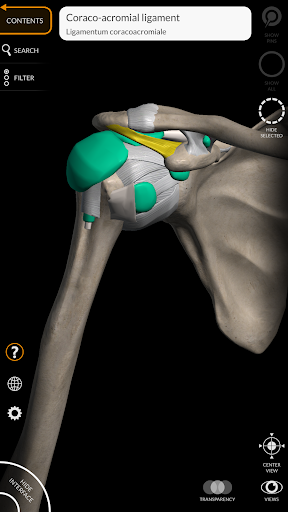

"Anatomy 3D Atlas" дозволяє легко та інтерактивно вивчати анатомію людини.

Завдяки простому та інтуїтивно зрозумілому інтерфейсу можна спостерігати кожну анатомічну структуру під будь-яким кутом.

Анатомічні 3D-моделі особливо деталізовані та мають текстури з роздільною здатністю до 4k.

• Вибравши модель або шпильку, з’явиться відповідний анатомічний термін

Ліги додані